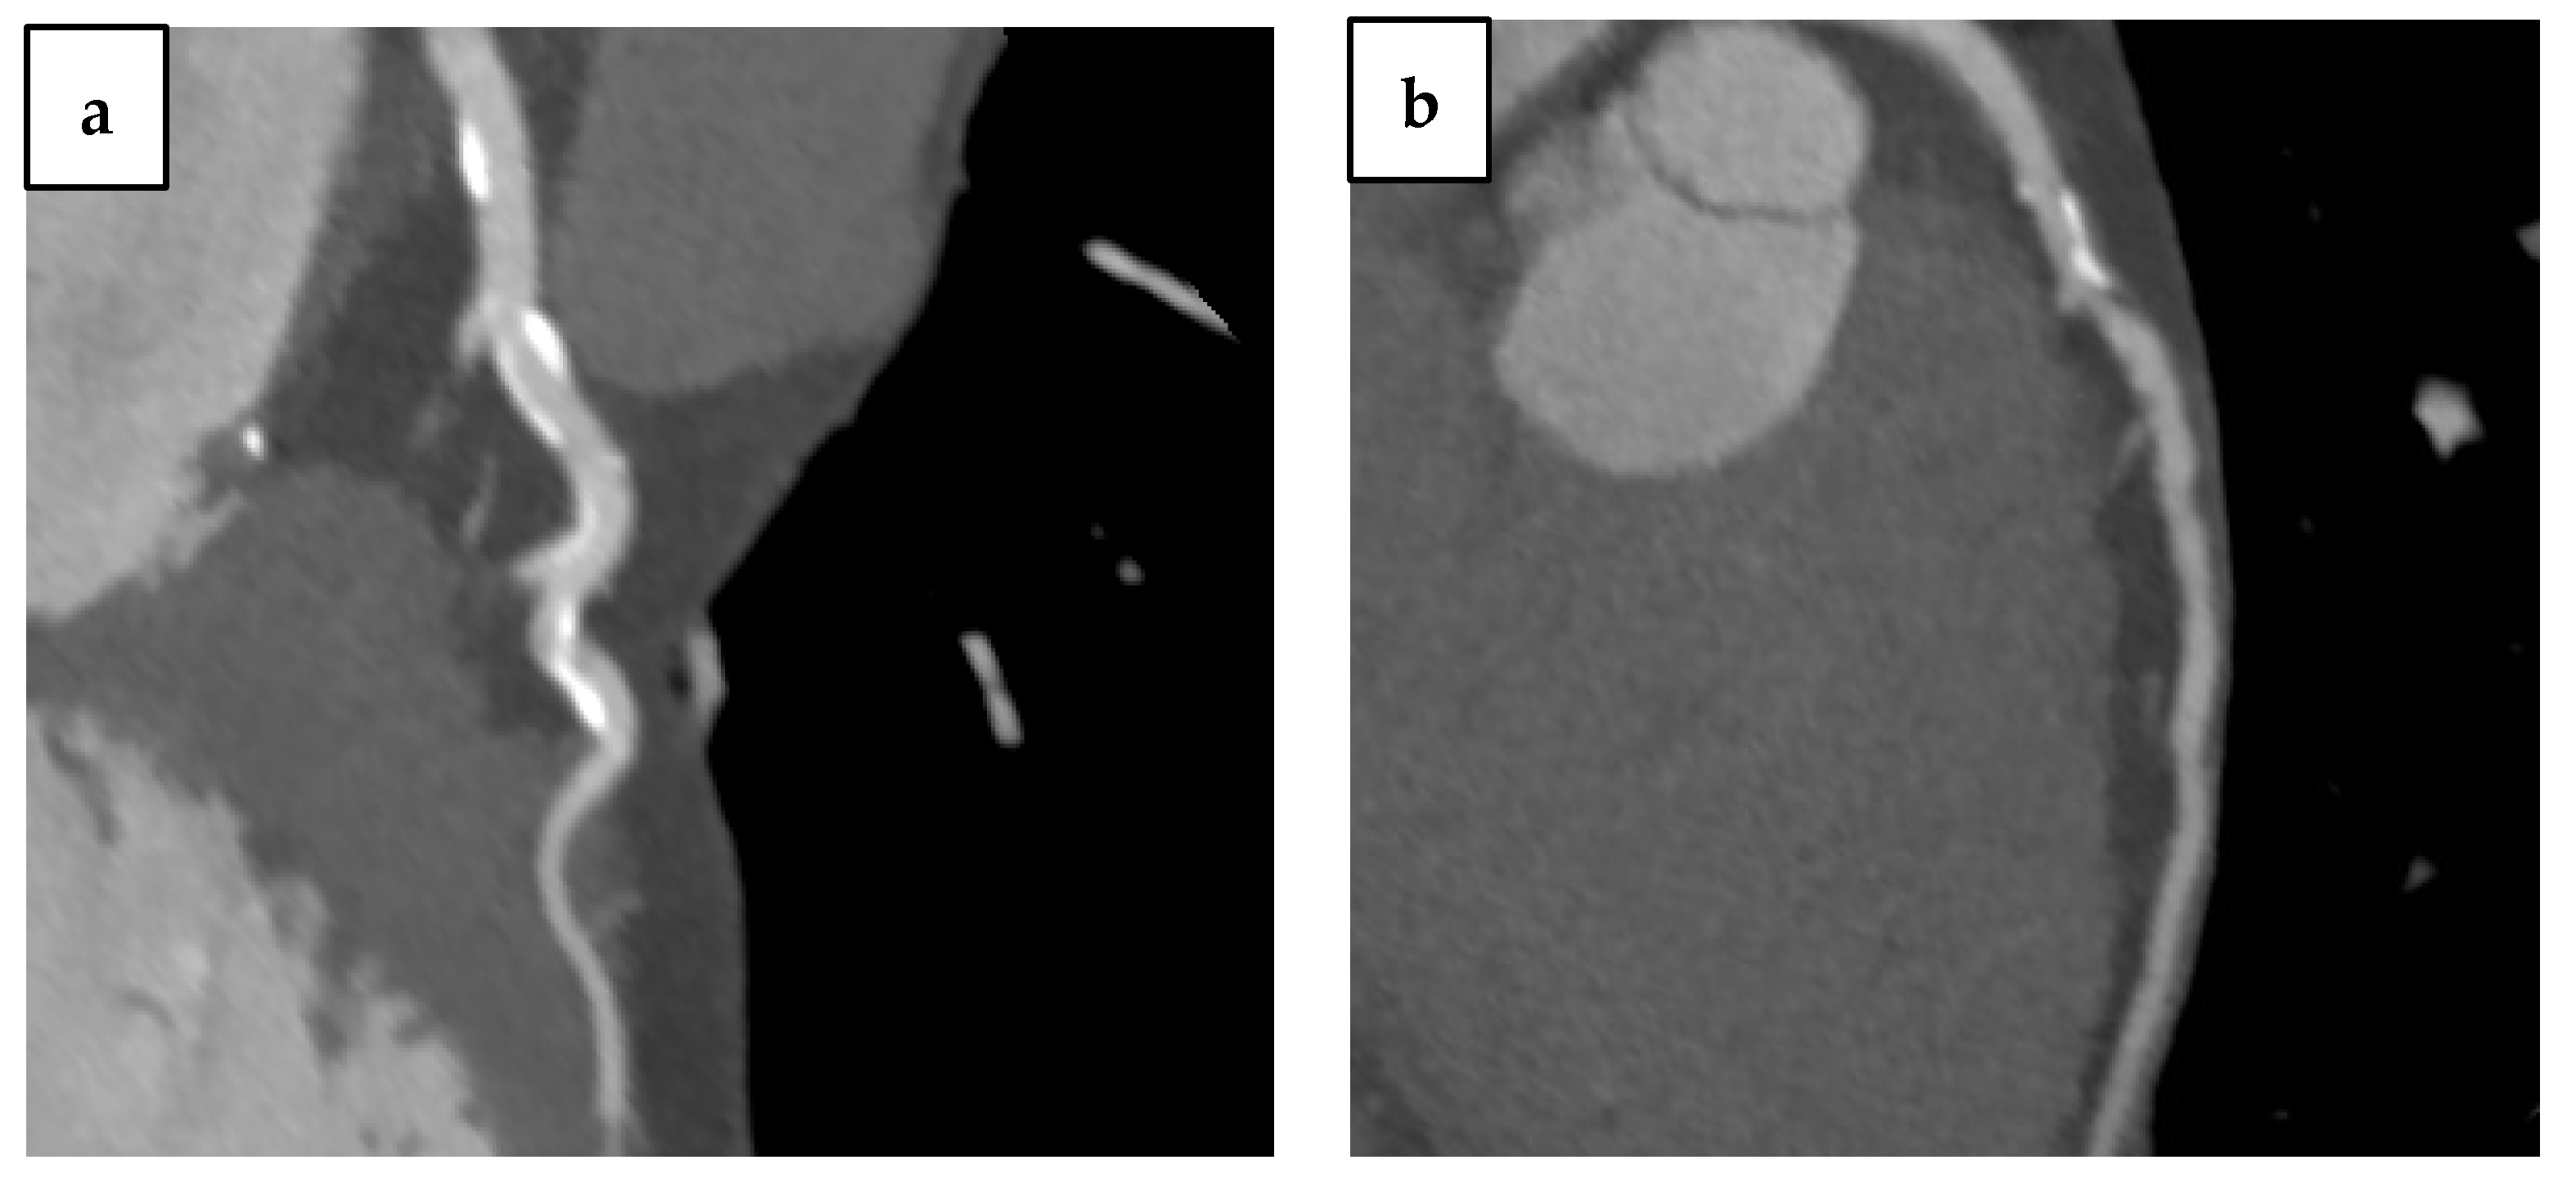

4.1. Aortic Calcium